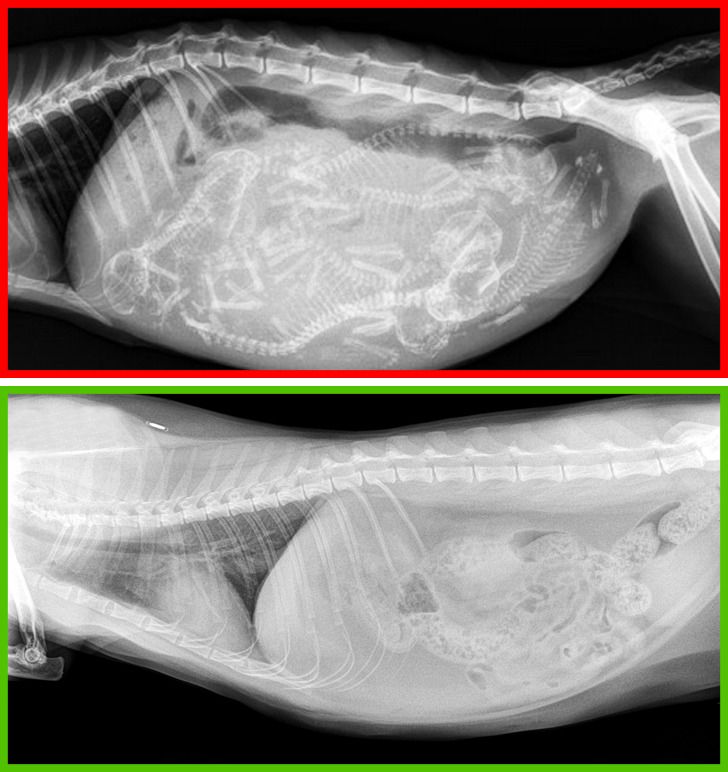

Fent egy várandós macska röntgenképe, alul egy ivartalanítotté látható.

Ezek az eljárások legtöbb esetben pozitív hatással van a háziállatok testére. A macskákban például csökken az emlőrák és a hererák kialakulásának kockázata, ráadásul a kasztrált macskák ritkábban szöknek el otthonról vagy mutatnak agressziót.